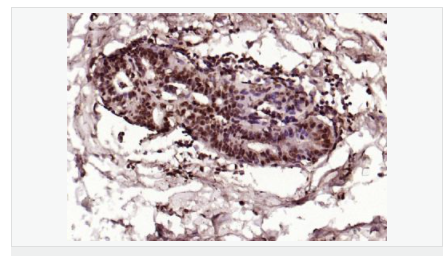

交叉反應:Human,Mouse,Rat(predicted:Dog,Pig,Rabbit,GuineaPig) 推薦應用:IHC-P,IHC-F,ICC,IF,Flow-Cyt,ELISA

| 產品應用 | ELISA=1:5000-10000 IHC-P=1:100-500 IHC-F=1:100-500 Flow-Cyt=1μg/Test ICC=1:100 IF=1:100-500 (石蠟切片需做抗原修復) not yet tested in other applications. optimal dilutions/concentrations should be determined by the end user. |